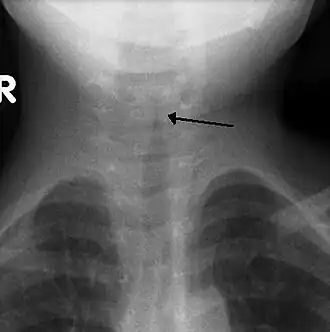

Une radiographie frontale du cou n'est pas systématiquement réalisée mais, si elle est faite, elle peut mettre en évidence l'étrécissement caractéristique de la trachée, réalisant le signe du Clocher. Le signe du Clocher oriente le diagnostic, mais il est absent dans la moitié des cas.